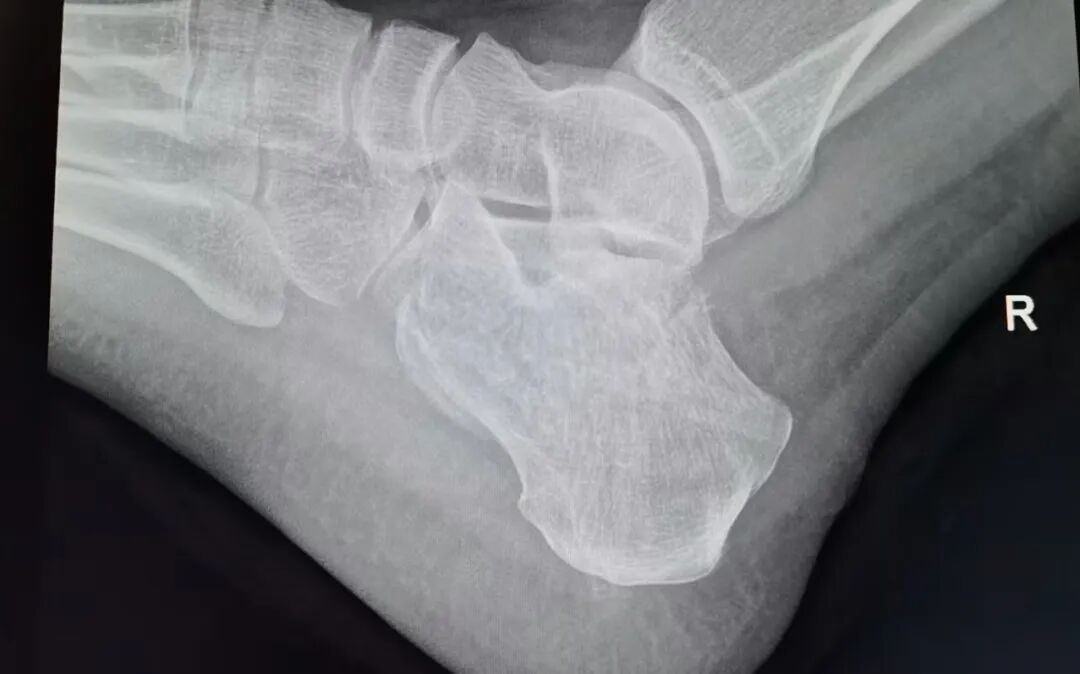

该男性患者因右足高出跌落伤1小时入院。入院时右足肿胀明显,宽度增加,触痛明显,CT显示骨折移位明显。以往常规治疗需要等肿胀消退之后,大约5-7天,才可以进行手术治疗。

术后复查影像